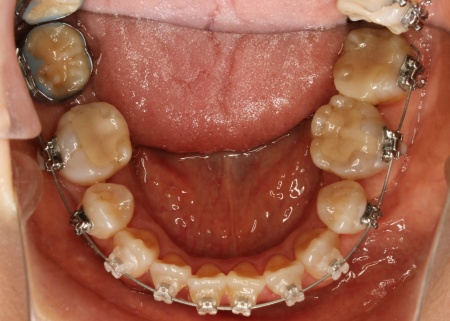

治療中